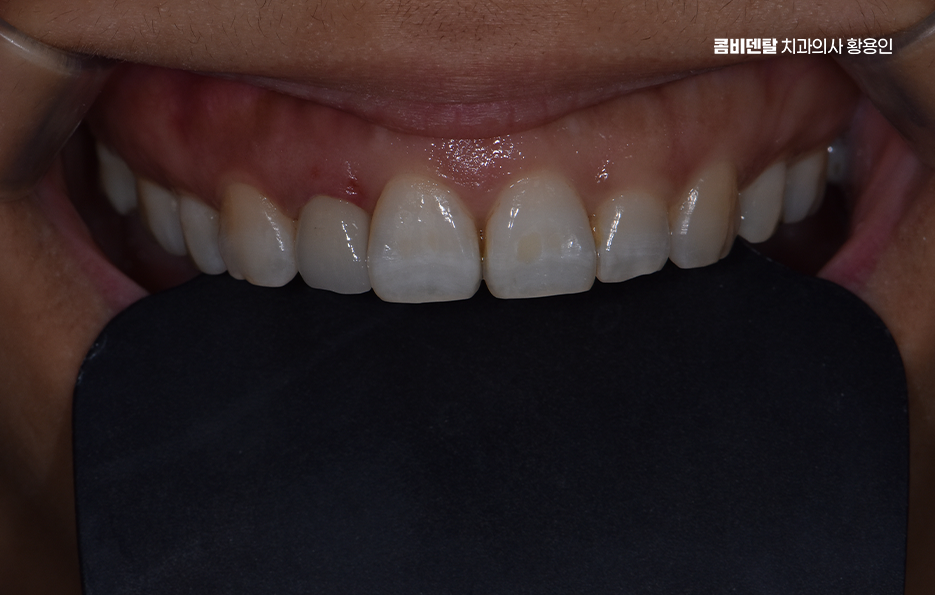

앞니는 사람의 얼굴에서 먼저 눈에 띄는 부위이기 때문에 심미적인 부분이 아주 중요한데 충치가 심하거나 깨지거나, 색이 변해버린 앞니를 그냥 두기에는 부담스럽고, 치료를 하더라도 주변 치아와 똑같이 자연스럽게 보여야 하다보니 이런 앞니에 적합한 보철치료 방법이 바로 앞니 올세라믹 크라운 치료라고 할 수 있어요

올세라믹이라는 건 말 그대로 금속이 전혀 들어가지 않은 순수 도자기 재질로 만들어진 보철물을 말하는데 금속이 없기 때문에 빛이 투과되는 방식이나 색상의 자연스러움이 실제 치아와 거의 흡사해서, 앞니처럼 시선이 집중되는 부위에 사용하면 주변 치아와의 경계가 거의 티 나지 않게 복원이 가능하며 특히 사진 찍을 때나 밝은 빛 아래에서도 회색 그림자나 반사광이 없기 때문에 심미적인 치료가 가능하다고 볼 수 있어요

앞니 올세라믹 치료는 과정을 살펴보면 우선 정확한 진단이 필요한데 현재 치아 상태가 올세라믹으로 치료 가능한지, 신경치료가 필요한지 여부와 치아 삭제량은 어느 정도로 해야 하는지 등을 평가하며 특히 앞니는 단순히 하나의 치아만 보지 않고, 양옆 치아와의 길이, 색상, 형태, 그리고 웃을 때 보이는 ‘스마일라인’까지 함께 고려해야 하기 때문에, 치료를 하기 전에 충분한 상담과 앞니 올세라믹의 특징에 대한 올바른 이해가 필요한 거예요

앞니 올세라믹 마지막 단계는 완성된 올세라믹 크라운을 치아에 접착하고, 교합을 조정하는 마무리 단계로 이때 중요한 건 주변 치아와 얼마나 조화롭게 어우러지는지를 보는 거예요. 색상은 단순히 ‘흰색’ 하나로 결정되는 게 아니라, 투명도, 밝기, 색조까지 섬세하게 조정돼야 하고 특히 앞니는 음식을 자르거나 말할 때 중요한 기능을 하기 때문에, 교합, 즉 맞물림이 정확해야 장기간 사용할 수 있어요.